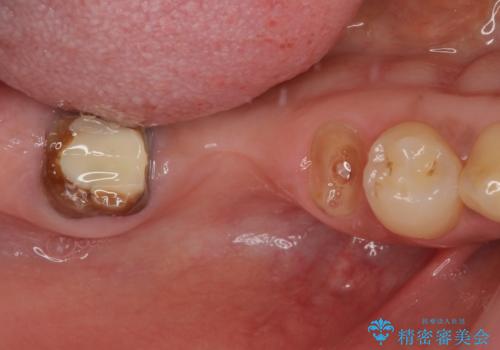

- クラウンを装着したばかりの歯の歯肉が腫れていることを気にして来院された患者様です。

むし歯がとても大きく、歯茎に歯の一部が埋もれてしまっているため、汚れが溜まりやすくなっている状態でした。